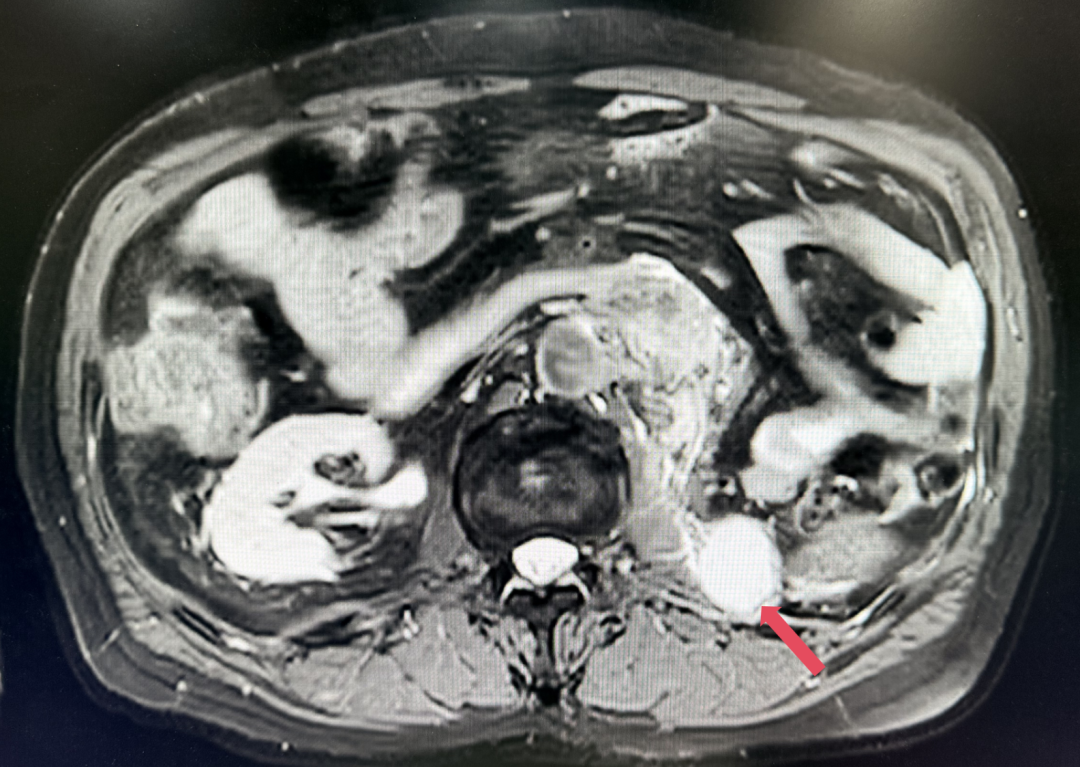

2023年11月:治疗10个月(C15)评估,肿瘤负荷减少至41mm,维持PR。

2023年11月,最深应答

患者初诊时68岁,2020年9月因“体检发现左肾占位2年”行腹腔镜下左肾根治性切除术,术后病理提示为肾透明细胞癌,pT3aN0M0,未行术后辅助治疗、未规律复查。2022年3月胸腹盆CT示腹膜后转移,IMDC评分0分,低危组。随后予一线培唑帕尼治疗,最佳疗效SD,2022年11月PD。于2023年1月经筛选进入Ⅲ期FRUSICA-2临床研究,开始接受呋喹替尼联合信迪利单抗二线治疗,用药6周(C2)后首次肿评即实现疗效PR(缩瘤率40.2%),用药10个月时缩瘤率近七成(68%),并维持上述水平至今,PFS已经超过37个月,在二线治疗中实现了长期无进展生存。同时,患者对呋喹替尼联合信迪利单抗方案耐受性良好,仅见轻微蛋白尿和偶然腹泻,未见其他不良反应,也未见免疫治疗相关不良反应。该方案有望为TKI经治的晚期肾癌患者带来新的选择,为实现长期生存提供可能性。